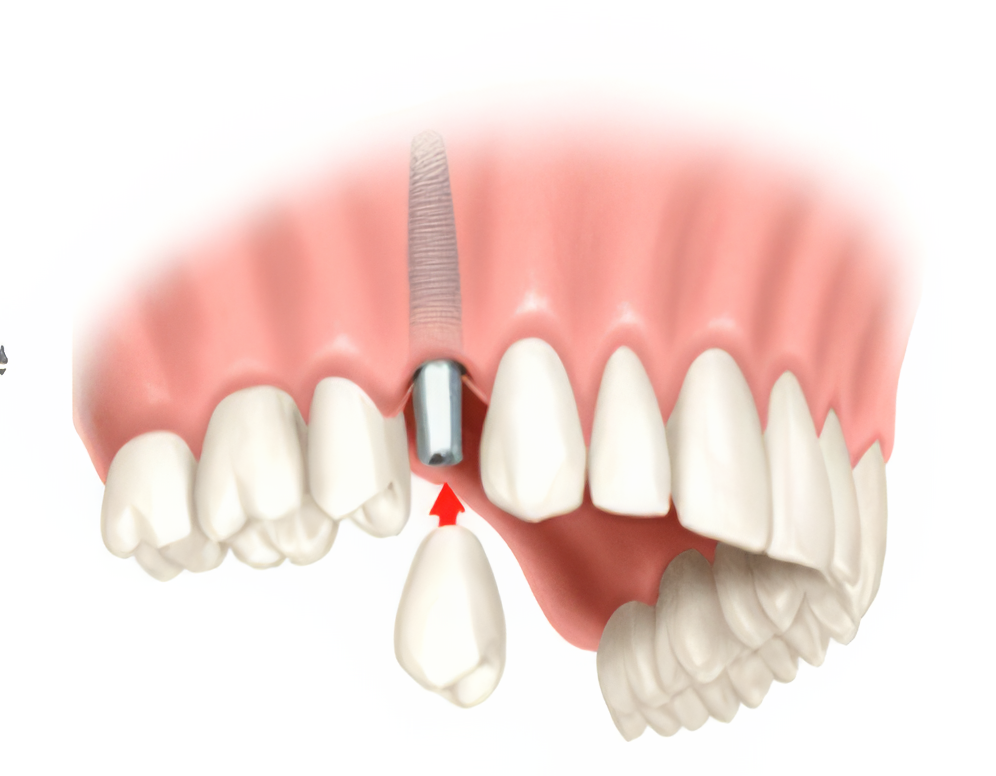

The procedure starts with developing a treatment plan to match your needs. Then an artificial root, which is a tiny post made of titanium, is installed in your jawbone. It takes 6 to 12 weeks for the bone to heal, and after that an abutment (a small connector post) is attached to securely hold the needed dental prosthesis.